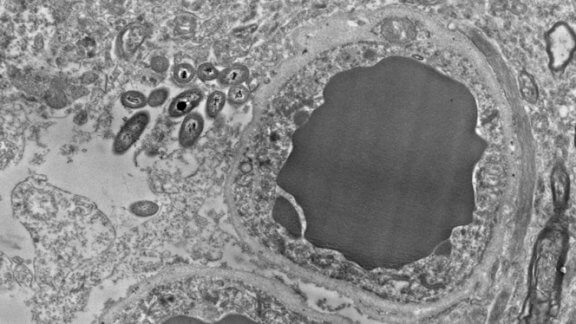

São células gliais de apoio aos neurônios, os astrócitos, os que impedem a entrada de neurotoxinas e outras substâncias ao cérebro. Estas substâncias danosas, quando conseguem ultrapassar a barreira de alguma forma, costumam provocar inflamações com consequências muito negativas e inclusive mortais. O curioso é de que os astrócitos parecem ser o lugar favorito destas bactérias intestinais para viver no cérebro.

Tanto em um quanto no outro estudo, foi observada a presença de bactérias no cérebro humano e no dos ratos, em situações não infecciosas ou traumáticas. De fato, foram encontradas em várias zonas cerebrais. Principalmente na matéria negra, no hipocampo e no córtex pré-frontal, e pouca quantidade no estriado. Além disso, nenhum dos cérebros examinados mostrava inflamação.

Imagem principal de Rosalía Roberts, Courtney Walker e Charlene Farmer